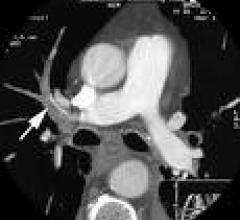

It’s no secret many clinicians have predicted coronary CT angiography (CCTA) would replace invasive angiography for…

March 9, 2009 - The use of dual-source computed tomography (DSCT) may be useful to noninvasively detect in-stent…